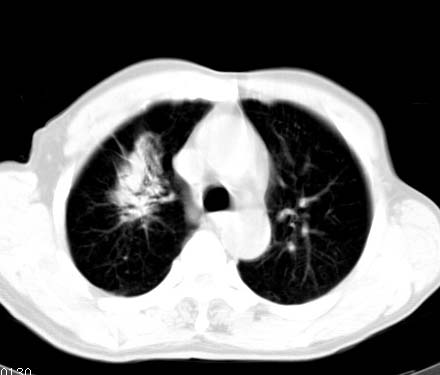

标题: CT14027:男性病人 71岁 咳嗽咳痰数周. [打印本页]

标题: CT14027:男性病人 71岁 咳嗽咳痰数周.

男性病人 71岁 咳嗽咳痰数周.诊断结核应该有保障吧!

右上肺结核,请结合痰检除外活动期;右上叶支气管官腔狭窄建议支气管镜或抗僗后随诊除外堵塞性改变。

高度怀疑肺癌,强烈要求纤支镜检查。